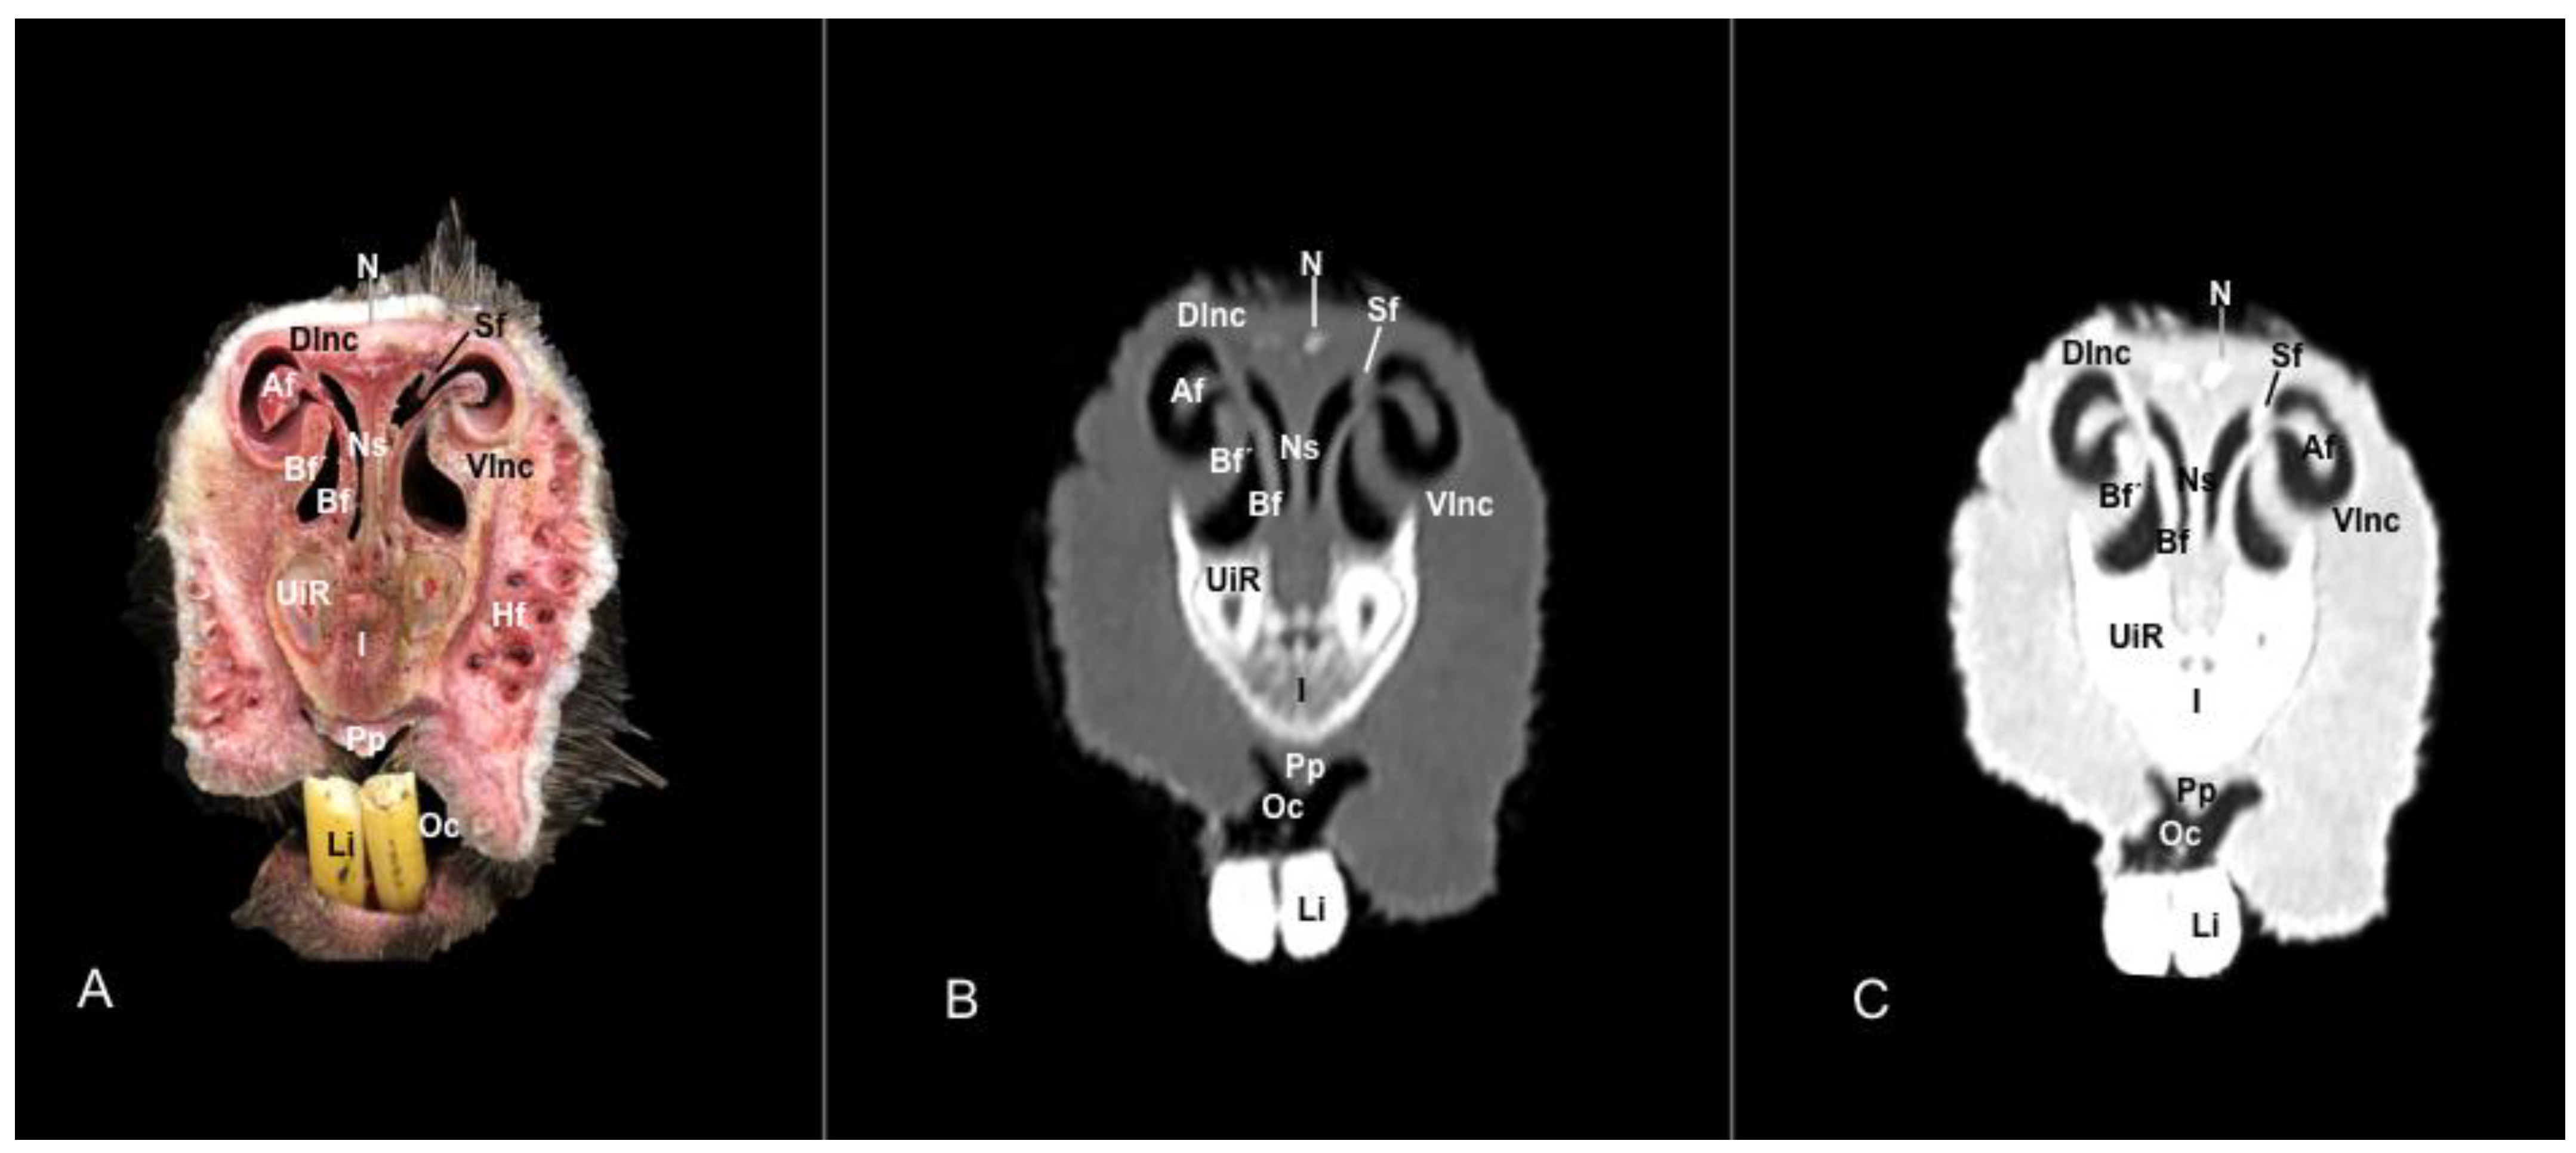

3.1. Anatomical Sections

3.2. Computed Tomography (CT)